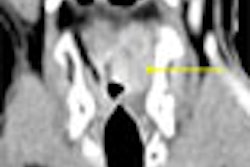

Thus, the current SIGGAR 1 trial is aimed in part at determining if VC can help fill the gap in colorectal cancer detection. Its stated goal is to assess the sensitivity and specificity of CT colonography (or virtual colonoscopy) in the per-patient detection of advanced adenomas or cancer in subjects age 55 and older at risk of colorectal disease.

The trial compares virtual colonoscopy with conventional colonoscopy and barium enema, which is still very popular in Europe. When performed correctly, barium enema can find about 85% of colorectal cancers and about 70% of advanced adenomas. But a national screening study found that sensitivity was just 48% for lesions greater 1 cm, Taylor said, so it may not be that good in practice.

At colonoscopy, polyps will be categorized as diminutive, small, and large. At VC only polyps 6 mm and larger will be reported to limit the number of false positives. The trial will also track "how many times colonoscopy misses lesions that CT sees first, costs, interobserver variability, and whether primary 2D or 3D is the best way to interpret the results," patient acceptance, and the frequency impact of extracolonic findings, he said.